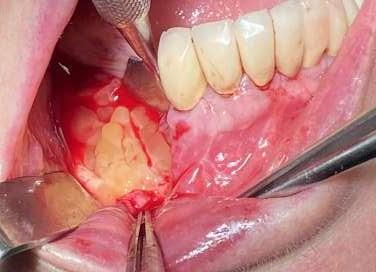

Trattamento dell’osteonecrosi mandibolare da bifosfonati

Ancora oggi non esiste un protocollo univoco di trattamento di questo tipo di complicanza e le motivazioni di questa assenza risiedono nella enorme variabilità della casistica tra paziente e paziente.

Ci sono però dei punti fermi su cui è ormai scontato che si debba fondare il proprio operato: pulizia, garantita dalla detersione profonda con l’utilizzo del PiezoClean®, e stimolazione alla guarigione indotta dal PRGF®3

La correlazione tra l’assunzione di bifosfonati orali e la comparsa di necrosi mandibolare è certa, così come certa è l’urgenza con cui è necessario intervenire su questo tipo di complicanza. Intercettare precocemente la problematica è possibile attraverso il follow-up. Appurata la presenza di una necrosi ossea, è indispensabile fornire all’organismo del paziente le corrette molecole antibiotiche per il trattamento e la prevenzione delle infezioni del sito chirurgico. Le complicanze di un mancato trattamento sono infatti gravi (es. compromissione del nervo alveolare, frattura di mandola, comunicazioni bucco-sinusali)2

È giunta per un ascesso con presenza di fistola drenante nel 4° quadrante ed è stata sottoposta a CBCT che ha rivelato la presenza di una necrosi mandibolare nella zona interessata dalla problematica ascessuale.

La necrosi, in estensione da 4.5 a 4.7, era stata precedentemente trattata con riabilitazione su impianti; sulla base di ciò è stata impostata la terapia antibiotica combinata con Amoxicillina+ac. Clavulanico e metronidazolo.

Mediante l’esecuzione di un lembo trapezoidale è stato possibile avere accesso all’intera zona necrotica, con buona visibilità del campo, nonostante la scarsa apertura buccale.

Dopo aver scollato ed esposto la zona, mediante l’uso dello strumento ultrasonico si è rimossa la porzione necrotica.

Per questa azione di toelettatura sono stati adoperati gli inserti Esacrom ES052XGT e ES010T.

Verificata la completa rimozione del tessuto malato e appurato il ripristino della vascolarizzazione del sito, è stato ulteriormente deterso mediante una applicazione della durata di 60 secondi dell’inserto PIEZOCLEAN, il cui utilizzo produce detersione profonda della zona su cui viene applicato. Infatti il dispositivo, in silicone sterilizzabile in

Al termine della toelettatura, sono state posizionate le due frazioni di PRGF e si è effettuata sutura interna con Vycril 4/0 ed esterna con seta 4/0.

L’immagine finale mostra lo stato della mucosa a distanza di 1 anno.